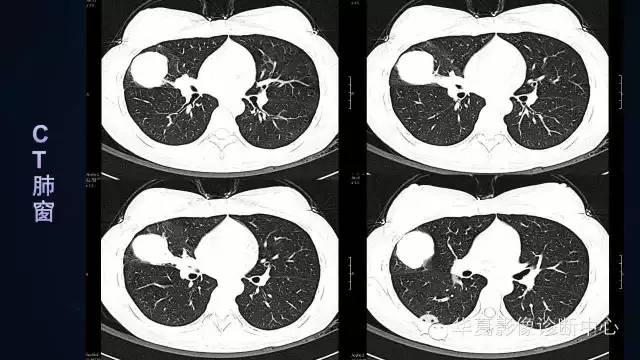

【病例】肺肉瘤样癌1例CT影像表现